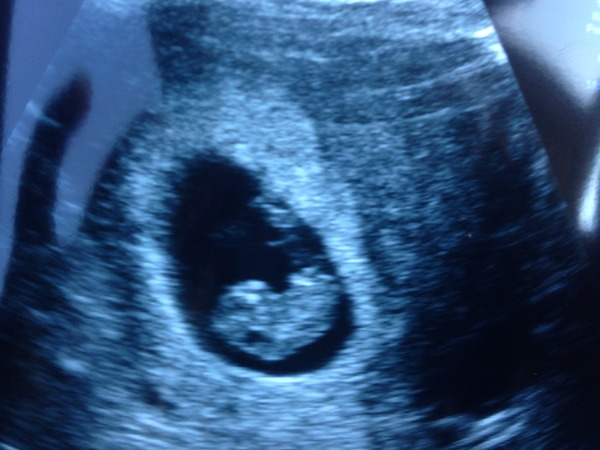

Might aswell join in and add my scan. Just looks like a blob. Haha

Thanks smoke! How far along were you MGFM?

bounce I was 7 +5. The blob measured 1 cm with heartbeat which put me at 7 +1 but I am sticking with my original dates until dating scan in September. And according to my app the blob is now technically a foetus!